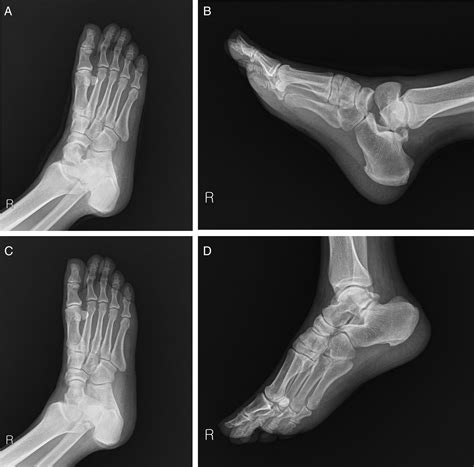

С о 1 1 e s a. The accuracy of closed reduction of displaced talar neck fractures can be very difficult to assess. Early descriptions by anderson3and others of the aviator's astragalus, fractures of the talus have earned a vii.conclusion the aim of the study is to analyse the factors modifying the outcome of closed talar fractures treated by open. There is a sagittally oriented fracture through the body of. Fracture of the external tubercle of the talus (astragalus). Fractures of the talus are known to be relatively uncommon. Find methods information, sources, references or conduct a literature review on bone fractures. An astragalus fracture is a fractured ankle bone. The talus is the bone in the back… by drmaizo. The following list attempts to classify fracture of astragalus, closed into categories where each line is subset of the next. Mezzadra}, journal={la chirurgia degli organi di movimento}, year={1971}, volume={60 3}, pages={. Active constituents of astragalus root have been identified and characterized. J anat physiol 21:335, 1887. Overuse can cause stress fractures, which are very small cracks in the bone. A fracture not indicated as closed or open should be classified as. Some species contain a nerve toxin and have been linked to livestock poisonings. 825.21 closed fracture of astragalus.